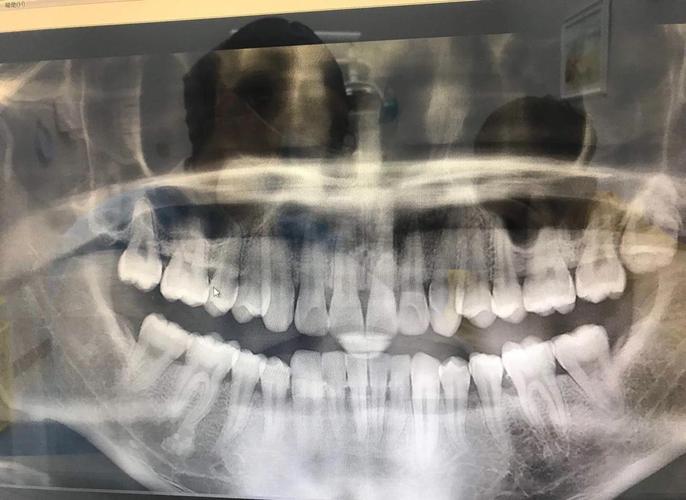

- 影像学评估:矫正前需拍摄全景片、CBCT等,明确智齿的位置、牙根形态、与邻牙及下颌神经管的关系,避免操作损伤神经或邻牙。